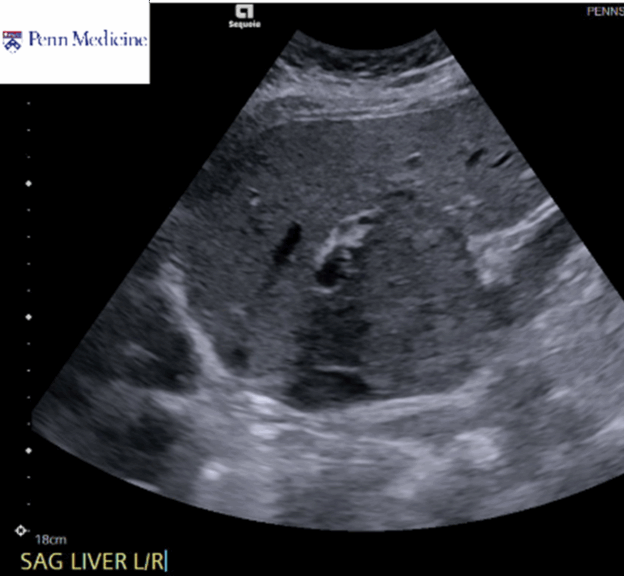

30-year-old woman with elevated liver function enzymes

A 30-year-old woman with no significant medical history presented for evaluation of elevated liver function enzymes identified during an annual physical.